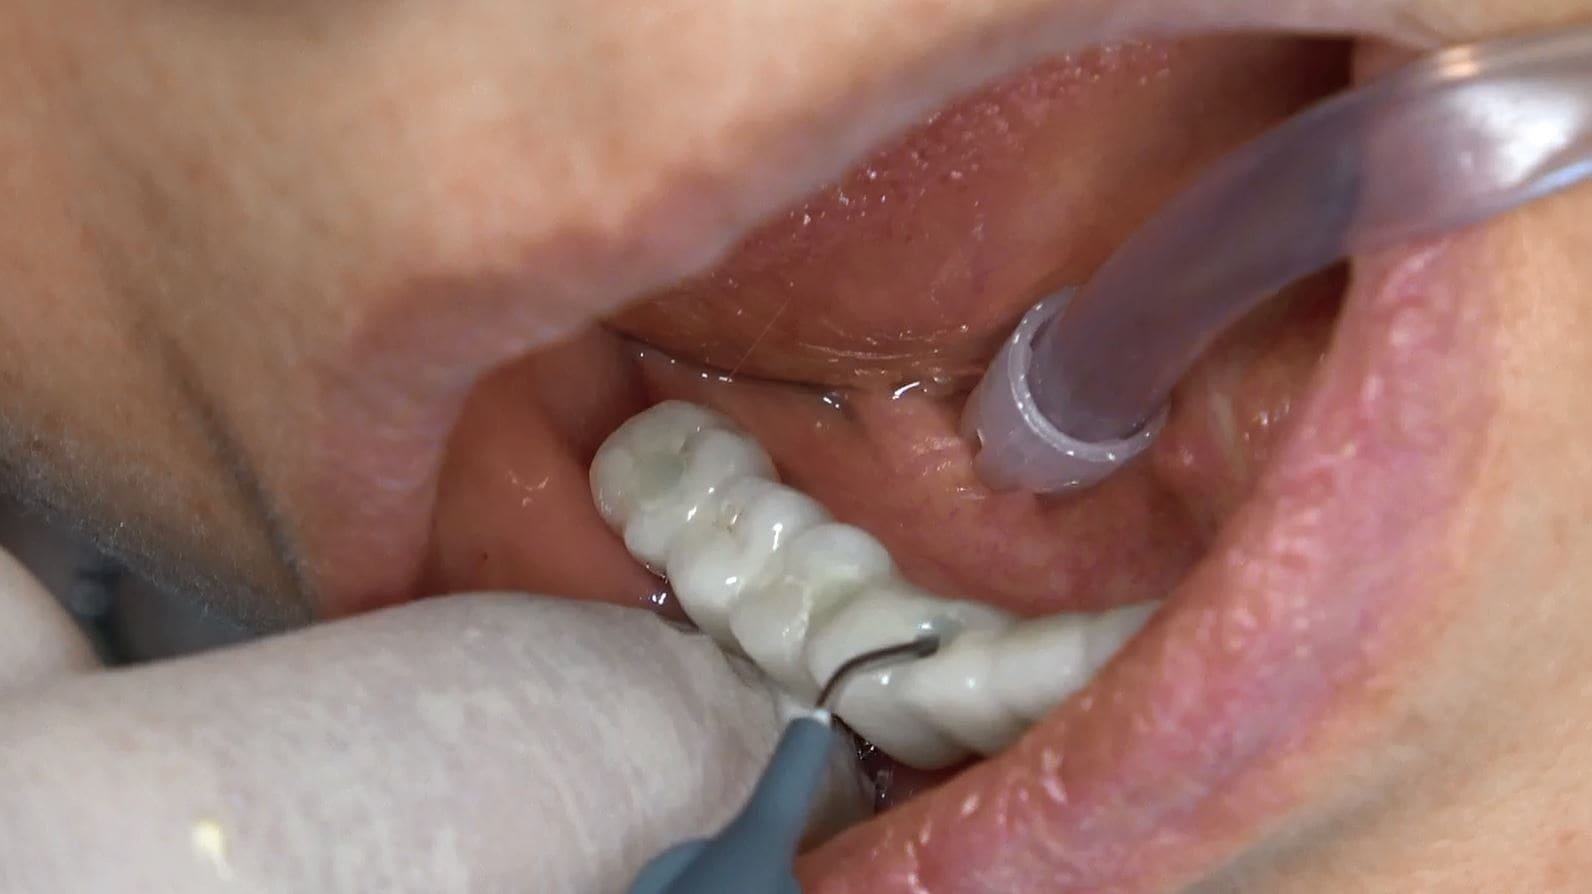

Segue cambio protesi da fissa provvisoria a fissa definitiva solo sotto, la parte superiore deve essere ancora sostituita con la protesi definitiva.

Protesi Provvisoria a Carico Immediato

Dopo l’intervento, vengono ancorate alla griglia delle protesi fisse provvisorie che consentono al paziente di avere denti fissi in sole 24 ore. Questo permette al paziente di tornare alle sue attività quotidiane senza dover aspettare mesi per ottenere una protesi definitiva.

Dopo circa 6 mesi, una volta completata la fase di guarigione, viene realizzata e posizionata una protesi definitiva. Questa protesi può includere anche impianti pterigoidei per una maggiore stabilità e supporto. La protesi definitiva permette al paziente di avere un sorriso completo e funzionale, ripristinando la sua capacità di masticare e parlare correttamente.